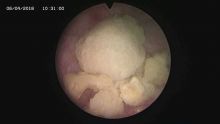

多镜联合治结石 4月6日,处于休假期间,但绥宁县人民医院泌尿外科的医护没有休息,在科主任张华生的带领下,打破常规,挑战高度,成功完成了一台复杂的结石手术。 据悉,患者姓杨,是一位60岁的男性患者,因"间断性左侧腰痛2年,再发伴尿痛2天"入院,经检查后发现患者左肾、左侧输尿管、膀胱内均有多发结石。针对这种结石,传统的手术方法至少需要开3刀,且需分期进行,使得患者痛苦大、治疗周期延长,费用也相应增高。肾结石开刀手术后劳动力会严重散失,即使采用现在流行的微创手术,常规也得分期进行,患者免不了多次手术的痛苦。为进一步减轻患者痛苦,绥宁县人民医院泌尿外科的医师们经过慎重考虑,决定打破常规,制定了多镜联合取石的手术方案。手术在4月6日顺利进行,术中联合膀胱镜、输尿管镜、经皮肾镜进行了长达70分钟的治疗,使得出血量不超过5mL且伤口仅0.5cm,一次性将患者膀胱,左侧输尿管,左肾结石全部取出。术后第五天经复查无任何结石残留,4月13日患者顺利出院。 目前,绥宁县人民医院泌尿外科在微创手术治疗各种尿路结石的技术上,己非常熟练。结石在整个邵阳地区发病率都很高,平常多喝水,每天饮水2000ml以上,调节饮食生活习惯,坚持锻炼可以有效预防结石发生,定期的健康体检也是预防结石的有效措施之一,可以早期发现结石,及时治疗。(图文 付志峰 编辑 谢雅玲) 图为:泌尿外科主任张华生、副主任付志峰进行手术时场景 图为:膀胱结石显象→手术碎石中显像→膀胱结石碎石后显像 图为:输尿管结石显像→输尿管结石碎石后显像 图为:肾结石显像→取出的肾结石标本 图为:术中建立穿刺通道 图为:术后留置的引流管 图为:术后伤口情况 |